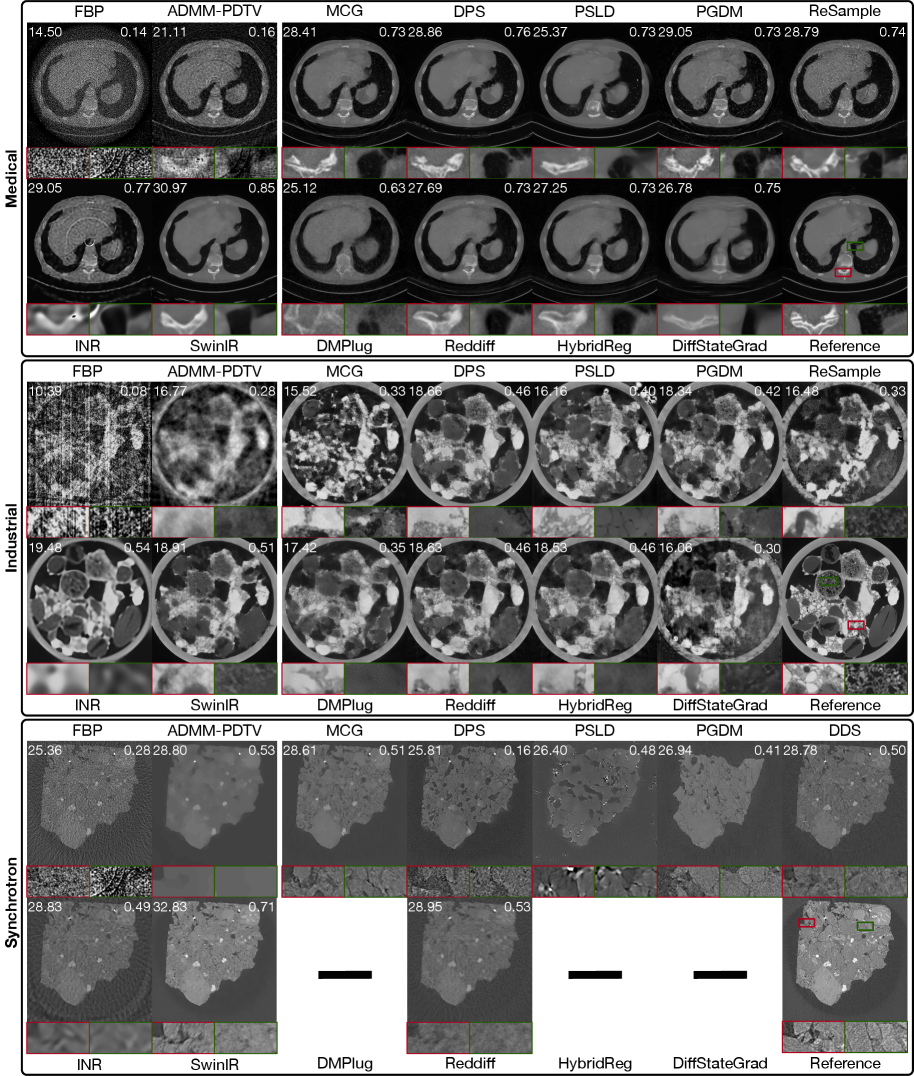

Refer to caption

Figure 2: Reconstruction results of diffusion-based and other established methods. Top: medical dataset (config iv, 80 angles with noise & ring artifacts); middle: industrial dataset (config ii, 20 angles with mild noise); bottom: real-world synchrotron dataset (60 angles). Red and green boxes show zoom-in regions. PSNR and SSIM appear in the top-left and top-right of each image. A dash (–) indicates that the method exceeded the 40 GB GPU memory limit for single-slice reconstruction and is therefore not executed. Images are consistently linear rescaled across methods to improve contrast.

Reconstruction Performance. As shown in Table 2, diffusion-based methods generally outperform classical and MBIR approaches in terms of PSNR and SSIM, but often fall short of fully supervised SwinIR. The INR-based approach achieves comparable metrics to diffusion methods, particularly in the noiseless scenario (config i) and on the real-world dataset. Visual examples in Figure 2 reveal that diffusion models tend to recover fine structural details that appear realistic but may diverge from the true reference, thereby reducing metric alignment. In contrast, INR and SwinIR produce smoother reconstructions, resulting in higher quantitative scores despite a loss of high-frequency details.

Among diffusion models, no single method or subclass (e.g., pixel vs. latent diffusion) consistently outperforms the others across all datasets and configurations, either visually or quantitatively. Performance on the real-world dataset is generally worse than on simulated data, likely due to factors such as limited training data quality and distribution shift. Perceptual metric LPIPS and full visual comparisons are discussed in Appendix A.14.

Impact of Measurement Sparsity and Measurement Noise. Figure 6 summarizes how different classes of reconstruction methods respond to variations in measurement sparsity and measurement noise. Diffusion-based methods, particularly pixel-space models, demonstrate clear advantages under sparse-view and high-noise conditions, where strong learned priors help compensate for limited or corrupted measurement information. The performance gap narrows as noise decreases or views increase, where classical and MBIR methods also become more effective.